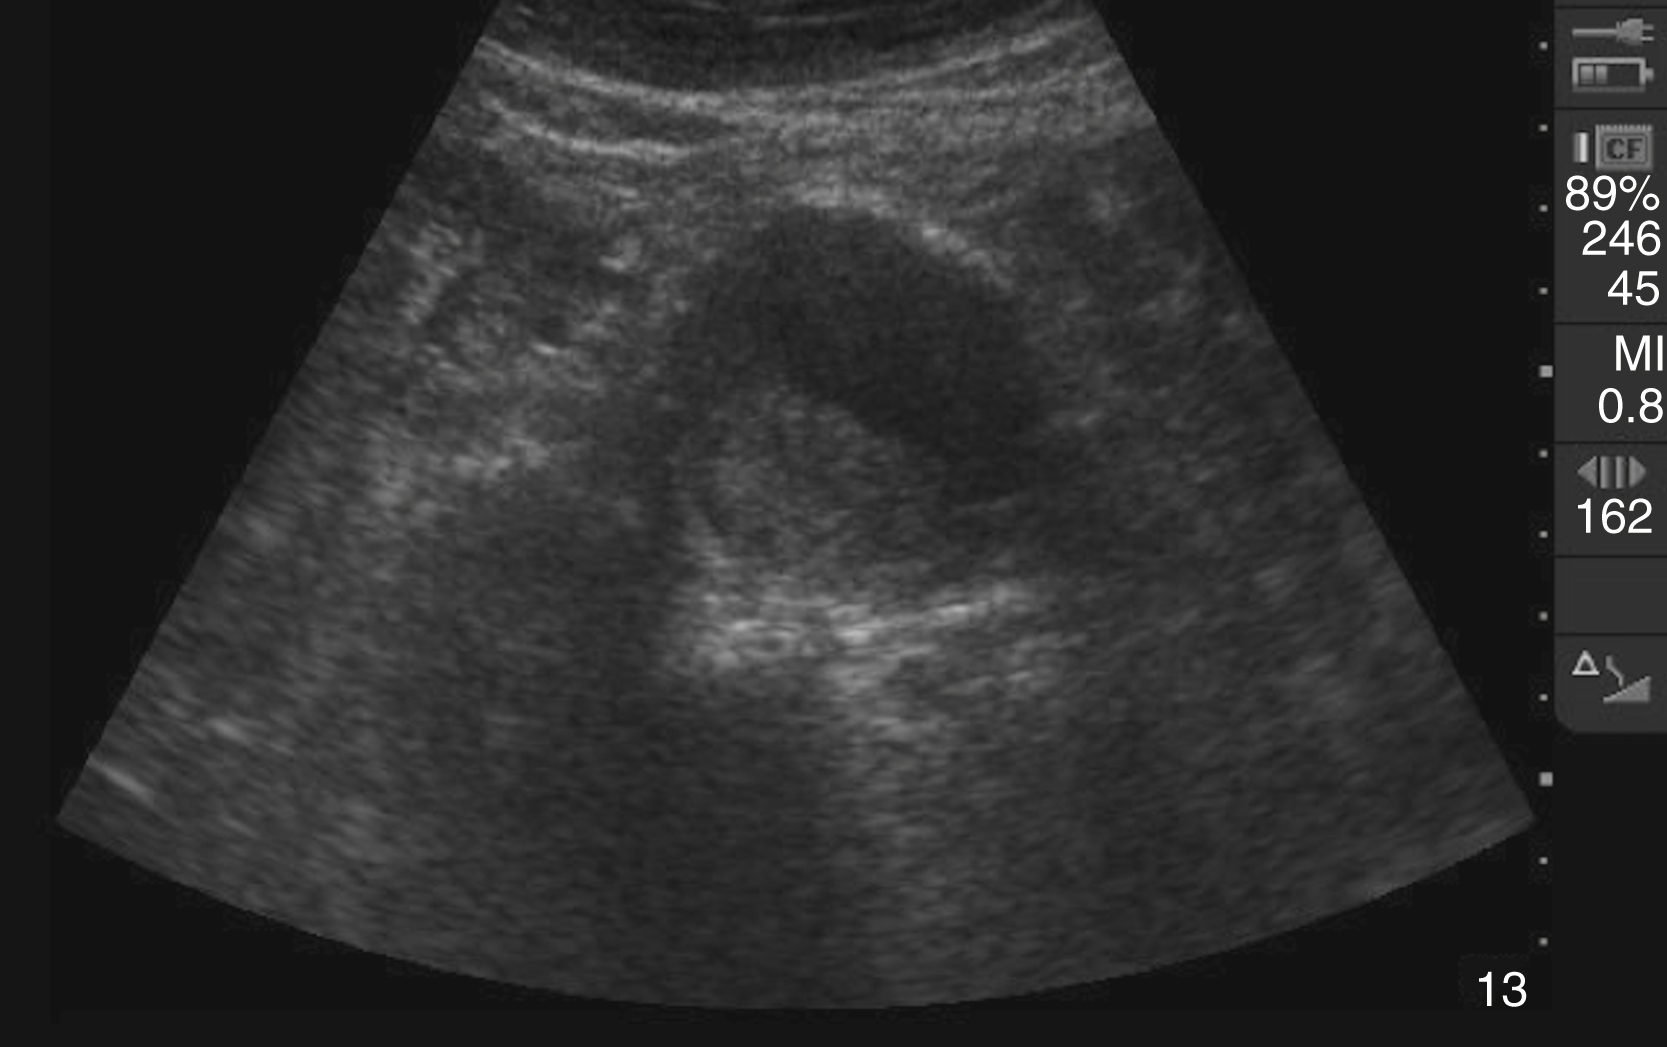

The diagnosis of cholelithiasis is made by identification of echogenic foci within the gallbladder lumen with associated shadowing. Other image patterns include stones with indistinct shadow, sludge, and the wall-echo-shadow (WES) sign seen in a gallbladder full of gallstones ( Video e3.5 ). Although many sonographic findings can be seen with AC, including gallstones, dilated gallbladder, increased gallbladder wall thickness (>3 mm), sonographic Murphy sign, pericholecystic fluid, and CBD dilatation, gallstones are present in 95% to 99% of AC cases ( Fig. e3.4 ). A nonmobile stone in the gallbladder neck, confirmed in the left lateral decubitus position, is highly suggestive of eventual cholecystitis. A CBD larger than 6 mm in people younger than 60 years and larger than 10 mm in older patients may indicate choledocholithiasis.

Fig. e3.4

Sagittal gallbladder with signs of acute cholecystitis including stones with posterior shadowing, thickening of the wall anteriorly, and pericholecystic fluid seen within the wall of the gallbladder.